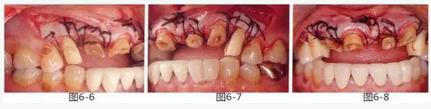

圖6-6~8

左上3到右上3的牙齒,通過包含牙槽骨外科處理在內(nèi)的APF進行治療,確保了獲得biologic width所必需的、3mm以上的健全牙體組織。為獲得附著齦,使用FGG對左上4和右上4的牙齒進行了治療。

圖6-9 牙周外科治療5個月后,最終取模前的狀態(tài)?;乐車@得了充足的附著齦。

圖6-10 佩戴最終修復(fù)體時的X光照片。